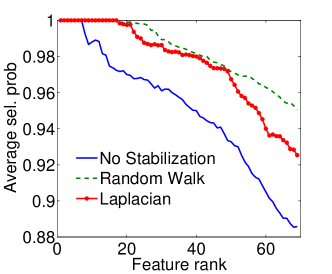

|

|

| (a) Cumulative, | (b) Stagewise (Shared), |

|

|

| (c) Stagewise (Separate), | (d) Stagewise (Separate), |

We now examine the models stability against data sampling and evaluate the stabilizing property of the proposed method (Sec. 6.2). For each fold, we generated samples, each of which was drawn randomly from % of training data. Each example resulted in a model, and the feature weights were recorded and finally the results of all folds – models – were combined. Figs. 5(a–d) show the indices (Eq. (5)) as functions of the rank list size , for all ordinal classifiers. The instability is clearly an issue – the average selected probability drops as more features are included. Using both the Laplacian and random walk regularization methods (Eqs. (9,10)), the improvement in stability is evidenced in all settings. The instability and stabilizing effect were similarly obtained with the indices (Figs. 6(a–d)).